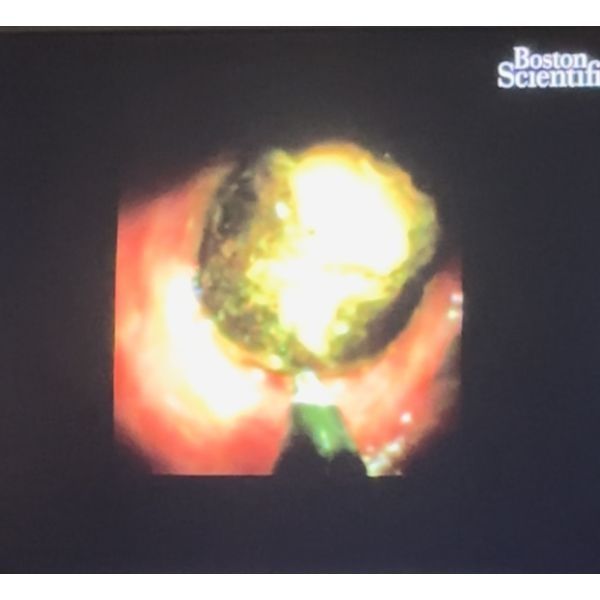

Однако извлечь крупные камни из общего желчного протока не удалось, поэтому через месяц пациент прошёл ещё одну операцию — наноимпульсное дробление камней (холедохолитотрипсию) с помощью аппарата SpyGlass.

По итогу операции крупные камни общего желчного протока были удалены. Все симптомы прошли, мужчина чувствовал себя хорошо.